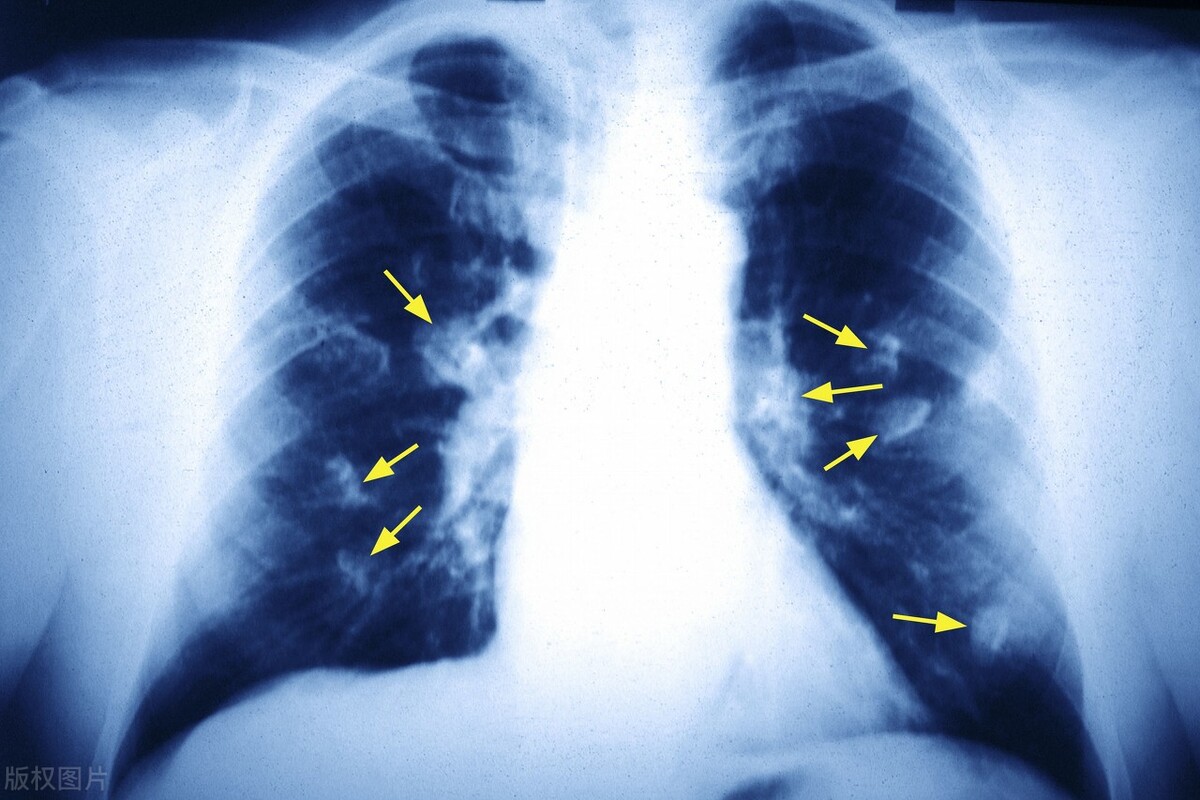

A.与其他国家相比,日本人吸烟习惯与较低的肺癌和心脏病发病率相关。尽管日本吸烟率居全球前列,但日本的肺癌死亡率却较低。与其他国家的吸烟者相比,日本吸烟者患心脏病的风险较低。